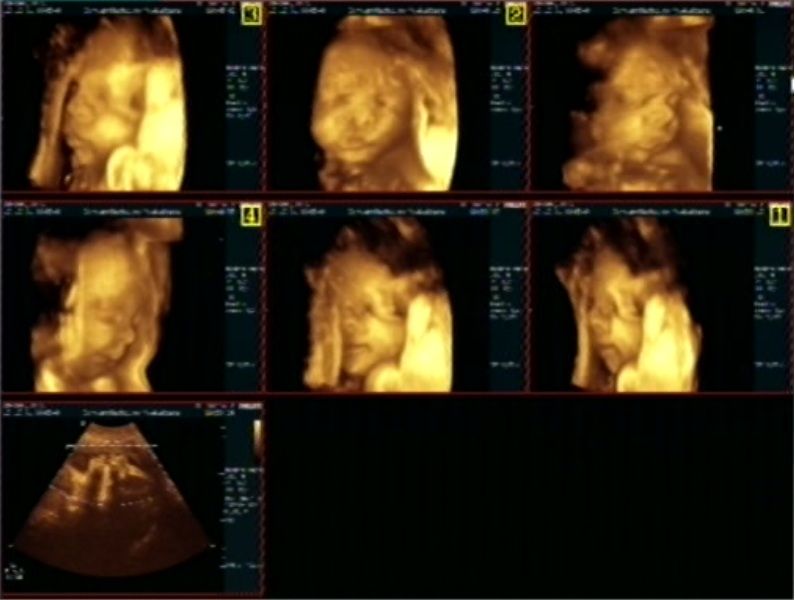

En nog wat overzichtjes:

Ze heeft nog een schatting gedaan naar het geboorte gewicht als het met 39-40 weken komt.

6 pond en 49 cm, niet zo'n groot kindje dus, waar ik toch best wel blij mee ben :)